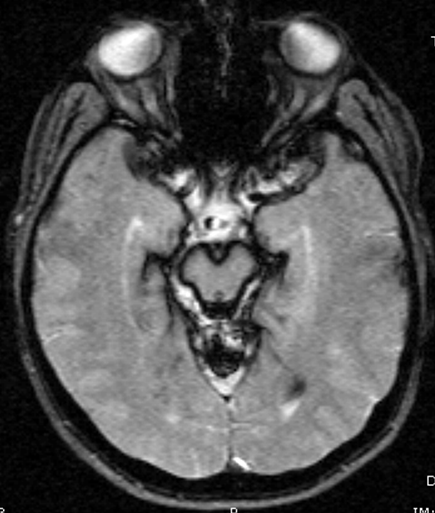

Paciente de 45 anos com ataxia progressiva de lenta instalação, liberação

piramidal global e perda auditiva bilateral. Histórico de 02

cirurgias cervicais anteriores por hérnia de disco.

A siderose superficial (SS) é causada por sangramento subaracnóideo crônico, sendo caracterizada pela deposição de ferro livre e hemosiderina nas estruturas piais e subpiais do sistema nervoso. A SS causa uma lesão progressiva e irreversível do sistema nervoso. As causas mais comuns de hemorragia subaracnóidea crônica são tumores, trauma de crânio e da coluna cervical, malformações arteriovenosas e aneurismas. A SS clinicamente é caracterizada pela tríade de surdez neurossensorial, ataxia cerebelar e presença de sinais piramidais. A RM de crânio e coluna cervical é o exame de escolha para se investigar e diagnosticar esta entidade clinica e os achados típicos são hipointensidades na sequencia T2 vistas ao redor do cérebro, cerebelo, tronco cerebral, medula e oitavo nervo craniano e algumas vezes também com a presença atrofia do cerebelo e medula. Não existe um tratamento de consenso para esta alteração.